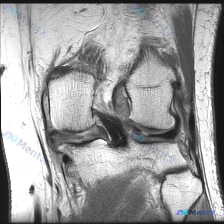

今天整理了一张膝关节MRI的读片分析,这个病例的思路很有代表性,分享给大家。 病例影像基础信息 这是一张膝关节MRI矢状位T1加权像,图像质量良好,对比度清晰,无明显伪影,层面可显示股骨髁、胫骨平台、交叉韧带等核心结构。 系统读片结果 1. 骨与软骨整体情况:股骨远端、胫骨近端骨髓信号均匀,无局灶低...